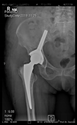

The guiding wire was inserted and controlled with fluoroscopy flashes (Figure 4). The drilling and reaming were carried out in accordance with the recommendations:

Figure 4.

The biocompatible aiming device after insertion of the guiding wire.

In all the cases operated with the above-described targeting procedure, the stems of the cups remained between the cortical bone surfaces without perforation of the linea terminalis, as shown by postoperative radiographs. There were no complicated surgical situations. In 16 cases, the wound healings were uneventful, and the hips were able to bear weight again after postoperative rehabilitation.